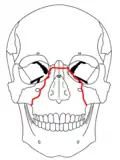

| Le Fort II fractures | |

At the beginning of the 20th century, René Le Fort mapped typical locations for facial fractures; these are now known as Le Fort I, II, and III fractures (right).[7] Le Fort I fractures, also called Guérin or horizontal maxillary fractures,[14] involve the maxilla, separating it from the palate.[15] Le Fort II fractures, also called pyramidal fractures of the maxilla,[16] cross the nasal bones and the orbital rim.[15] Le Fort III fractures, also called craniofacial disjunction and transverse facial fractures,[17] cross the front of the maxilla and involve the lacrimal bone, the lamina papyracea, and the orbital floor, and often involve the ethmoid bone,[15] are the most serious.[18] Le Fort fractures, which account for 10–20% of facial fractures, are often associated with other serious injuries.[15] Le Fort made his classifications based on work with cadaver skulls, and the classification system has been criticized as imprecise and simplistic since most midface fractures involve a combination of Le Fort fractures.[15] Although most facial fractures do not follow the patterns described by Le Fort precisely, the system is still used to categorize injuries.[5]